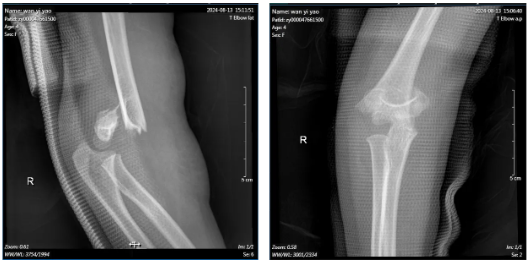

术前X线检查

几经辗转,抵达河池市人民医院后,创伤手外科副主任姚泓成详细询问病史、查体及结合影像学资料,明确诊断为“右肱骨髁上骨折(Gartland分型:Ⅲ型)”,有手术指征。考虑到孩子年纪小,且肘部肿痛明显、畸形严重,为减轻其痛苦,不留下终身的疤痕,创伤手外科团队组织了术前讨论,制定了详细的治疗方案,积极与家属沟通、完善术前准备后,姚泓成带领手术团队急诊为患儿实施右肱骨髁上骨折闭合复位克氏针内固定术+石膏固定术。